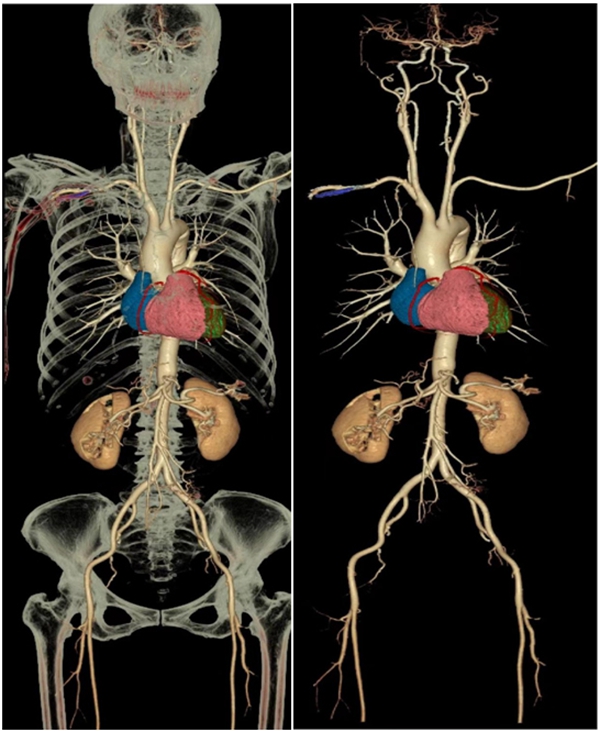

全身多部位大血管联合成像 注射一次造影剂即可

一次对比剂注射及CT扫描,即可获得多系统、多部位平扫、动静脉造影和灌注图像,如“4D全脑一站式”成像、胸痛三联、冠脉CTA+头颈部CTA等。

“一站式”检查,避免多次对比剂注射和分次检查,不但减少了射线辐射,也降低了反复使用对比剂诱发肾功能损害的风险,同时也满足临床对于疑难危重病例的快速诊断的需求。一次扫描可了解全身动脉血管的病变情况,特别适合健康人群中的高端体检。